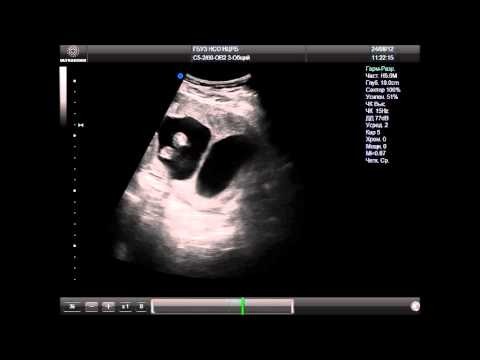

Обнаружить перегородку легко на ультразвуковом исследовании – треугольная ткань разделяет матку надвое. Полная перегородка – это масса проблем, поэтому многие специалисты рекомендуют убрать ее еще до зачатия. Если она неполная, то ее иногда оставляют, так как 50% женщин могут нормально выносить и родить малыша без патологий.

Врач регулярно осматривает пациентку, тщательно прослушивает сердцебиение плода и прощупывает размеры матки. Особую роль отводится УЗИ, которое, пожалуй, расставляет все точки. Самой беременной показано:

Ультразвуковое исследование (УЗИ)

Ультразвуковое исследование является одним из наиболее распространенных и доступных методов диагностики перегородки в матке. Оно позволяет визуализировать анатомическую структуру матки и выявить наличие перегородки. УЗИ может быть выполнено как трансабдоминально, так и трансвагинально. Трансвагинальное УЗИ обеспечивает более четкое изображение и позволяет лучше оценить состояние матки, особенно в ранние сроки беременности.